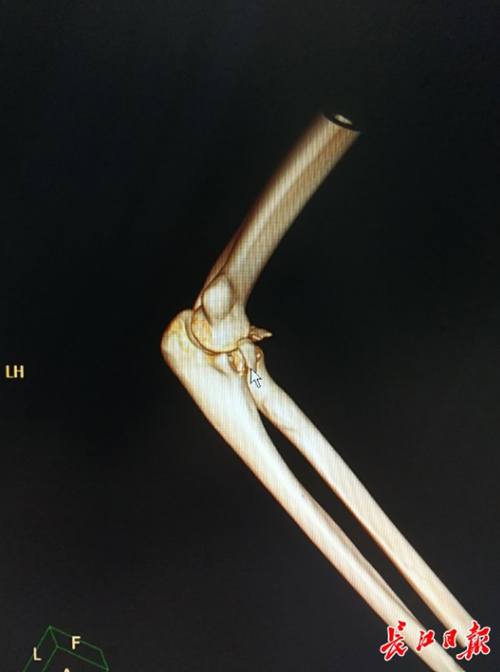

Phần khuỷu tay của Li Nan vừa bị trật khớp vừa bị gãy sau hành động lãng mạn bế người yêu. Ảnh: EBC.

Sau khi kiểm tra, bác sĩ nhận thấy phần khuỷu tay phải của Li vừa bị trật khớp vừa bị gãy. Tuy đã xử lý được chỗ trật khớp, Li vẫn cần phải được phẫu thuật do tình trạng của anh khá nghiêm trọng.